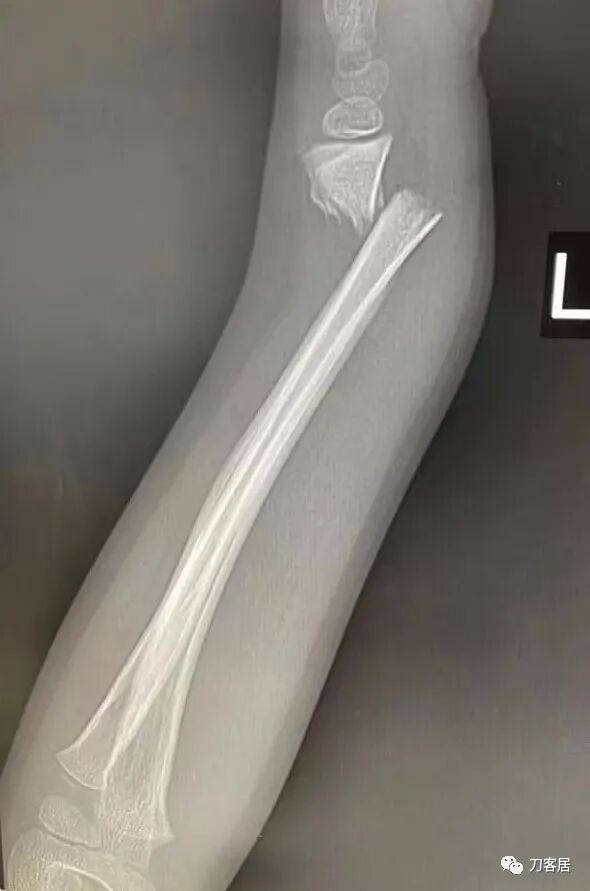

2021年7月22日晚,上海美华医院儿童骨科的师东良医生,给我提供了一例他处理的严重移位尺桡骨双骨折病例,经过手法复位,石膏外固定治愈。这个病例,其他医院建议要做手术。实际上,这样的病例,在现实中有太多太多,因为手法复位,石膏外固定治疗骨折,这是骨科医生的基本功。

超声引导下闭合手法复位石膏外固定治疗7岁患儿尺桡骨远端移位双骨折。

男,7岁,左前臂远端桡尺骨双骨折,术前X光片见图1,行超声引导下闭合复位石膏外固定术,康复训练,6周拆石膏,随访2.5月的效果。术后2.5X光片见图23。功能上仅前臂旋后较健侧减小15°,继续加强康复训练中。家长满意,评价见图4